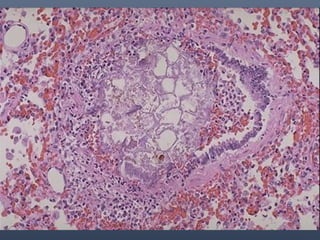

3.- Por lesión propiamente dicha en los pulmones, como ocurre en los

enfisemas pulmonares. (Anoxia anóxica).

Edema pulmonar

Combinación de hipoxia y elevación

de la presión en los vasos pulmonares

FISIOPATOLOGIA DE LASANOXIAS Hay cuatro causas principales de la anoxia: 1.- Por falta de oxigeno respirable. 2.- Por daño en el corazón que lo incapacita para bombear la cantidad de sangre suficiente. 3.- Por lesión propiamente dicha en los pulmones, como ocurre en los enfisemas pulmonares. (Anoxia anóxica). 4.- Por baja de glóbulos rojos, que son los encargados del transporte de oxigeno a los tejidos. (Anoxia anémica).

Edema pulmonar Fluidez dela sangre Ingurgitación de las cámaras derechas del corazón Combinación de hipoxia y elevación de la presión en los vasos pulmonares Coagulación post mortem de la sangre en el corazón y sistema venoso, eventual disolución de coágulos por acción de enzimas fibrinolíticas : procesos más irregulares e inconstantes Se encuentra en cualquier muerte congéstiva